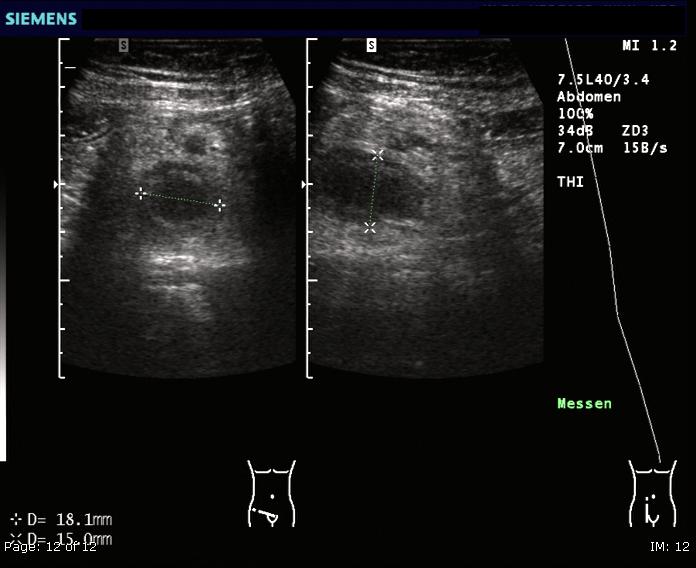

CT 스캔은 급성 충수염을 진단하는데 사용된다.[36] 의사는 환자의 병력과 증상을 평가하고, 신체 검사를 시행하며, 검사실 및 영상 검사를 모두 주문한다. 비전형적인 증상을 보이는 경우에는 초음파나 CT 스캔과 같은 영상 검사가 필요하다.[12] 소아는 방사선 노출 위험 때문에 초음파 검사를 우선적으로 시행하며, 결과가 불확실한 경우에만 CT 스캔을 추가로 시행한다.[54][55][56] 성인 및 청소년의 경우 CT 스캔이 초음파 검사보다 더 정확하며, 민감도 94%, 특이도 95%를 보인다. 반면 초음파 검사는 민감도 86%, 특이도 81%이다.[57]복부 초음파 검사, 특히 도플러 초음파는 특히 소아에게서 충수염 진단에 유용하다. 초음파 검사에서는 오른쪽 장골와에서 액체 저류, 컬러 도플러 사용 시 혈류 증가, 충수의 비압착성 등이 관찰된다. 급성 충수염의 다른 징후로는 충수 주변의 에코성 장간막 지방, 충수 결석의 음향 그림자 등이 있다.[58] 약 5%의 경우, 장골와 초음파 검사에서 이상이 발견되지 않지만, 이는 초기 충수염이거나 지방과 장내 가스로 인해 충수 확인이 어려운 성인에게서 흔하게 나타난다. 숙련된 검사자는 초음파 영상을 통해 충수염과 유사한 증상을 보이는 림프절 염증, 난소 또는 나팔관 문제 등을 구별할 수 있다.[60] 초음파 검사는 방사선과나 응급 의학 전문의가 시행할 수 있다.

충수염 진단은 충수 크기가 가장 중요하며, 6mm 이상이면 민감도와 특이도가 모두 95%이다.[65] 그러나 충수가 분변 물질로 채워져 팽창된 경우에는 진단이 어려울 수 있다.[66] 이 경우 초음파 검사가 유용하며, 주변 장에 비해 벽의 조영 증강, 주변 지방 염증 등의 특징으로 진단을 돕는다. 심한 경우 농성 염증, 고름집, 고름이나 장 내용물 누출로 인한 골반 내 액체 층이 관찰될 수 있다. 마른 환자는 지방 부족으로 충수와 주변 염증 관찰이 어려울 수 있다.[66]

CT 검사에서 충수 부종이나 주변 지방 조직 농도 상승이 관찰되며, 조영제 사용 시 민감도와 특이도가 모두 98%로 정확도가 높다. 최신 초음파 검사 장비는 맹장 형태 평가에 유용하지만, 맹장 위치나 장비, 검사자 숙련도에 따라 진단이 어려울 수 있다. 최근 소아 충수염 진단에서 컴퓨터 단층 촬영(CT) 검사는 감소하고 초음파 검사는 증가했지만, 임상 경과에는 변화가 없다는 보고가 있다.[126]